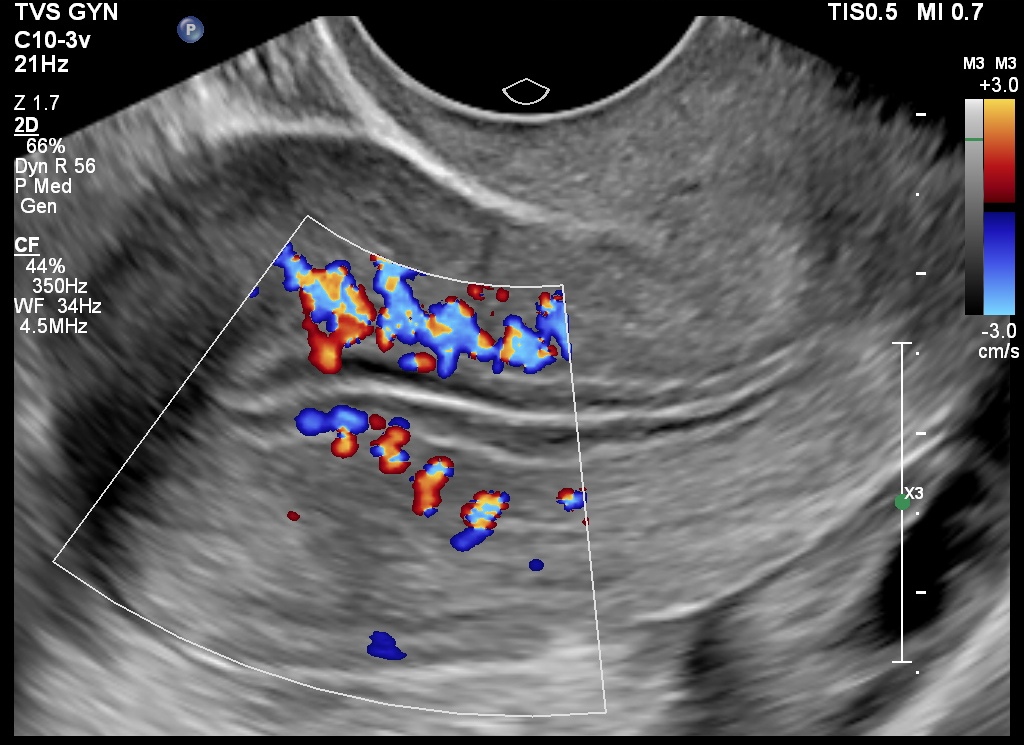

Women with a fertility problem are often asked by the Gynecologist to get follicular study done. This is a transvaginal ultrasound study which is done serially over several days. The ovaries and endometrium are examined to look for follicular growth and rupture and also to estimate the quality of the endometrium using certain parameters. This helps the gynecologist time the intra-uterine insemination or advise coitus. This is also a crucial part of an IVF programme.